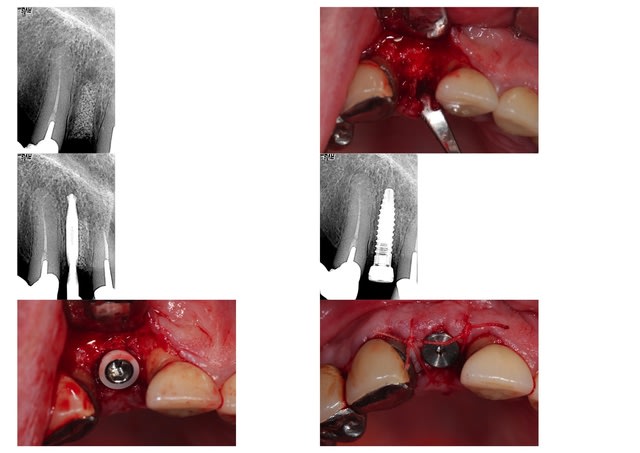

humator Ecrivait: > merci peach pour le diaporama. J'attend la > suite... >

la suite, la voici 5 mois + tard; la membrane de collagène a été exposée 10 jours + tard mais s'est finalement recouverte à 5 semaines post op bien que le ßTCP soit encore bien visible à la radio, j'ai accepté d'implanter à 5 mois sans plus attendre, pour satisfaire la demande du patient qui s'impatientait; évidemment, c'est discutable, mais dans la mesure où le TCP se résorbera un jour ou l'autre de toutes façons en laissant la place à del'os néo formé, j'ai accepté, en estimant que je ne devais normalement pas avoir de problème pour obtenir le fameux blocage primaire; effectivement, je l'ai eu à 40N/m, et avec une longueur de 13 mm, je suis serein; la paroi vestibulaire s'est bien reformée; le forage n'a pas été parfaitement centré, peut être parce que la dureté du site n'était pas uniforme, mais l'implant (ø 3,5mm) s'est recentré tranquillement au vissage (20 t/mn); tout est parfait à j+4; la suite suit... ! :-)